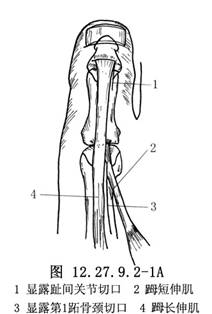

做“L”形切口顯露𧿹趾趾間關節(圖1a),將皮膚和皮下組織瓣向內、向近側拉開,找到𧿹長伸肌腱。在趾間關節近側1cm處橫斷肌腱,去除趾間關節面軟骨,用一根直徑爲0.2cm的斯氏釘或兩根直徑爲0.16cm的克氏針逆行固定,於皮下剪斷內固定針。另做一個2.5cm長的足背內側切口顯露第1蹠骨頸(圖12.27.9.2-1A),注意保護𧿹短伸肌腱,並沿切口全長切開其腱鞘。在第1蹠骨頸部位由蹠內側到外側橫向鑽孔,將肌腱經孔穿過,調整合適張力後與自身做間斷縫合(圖12.27.9.2-1B)。